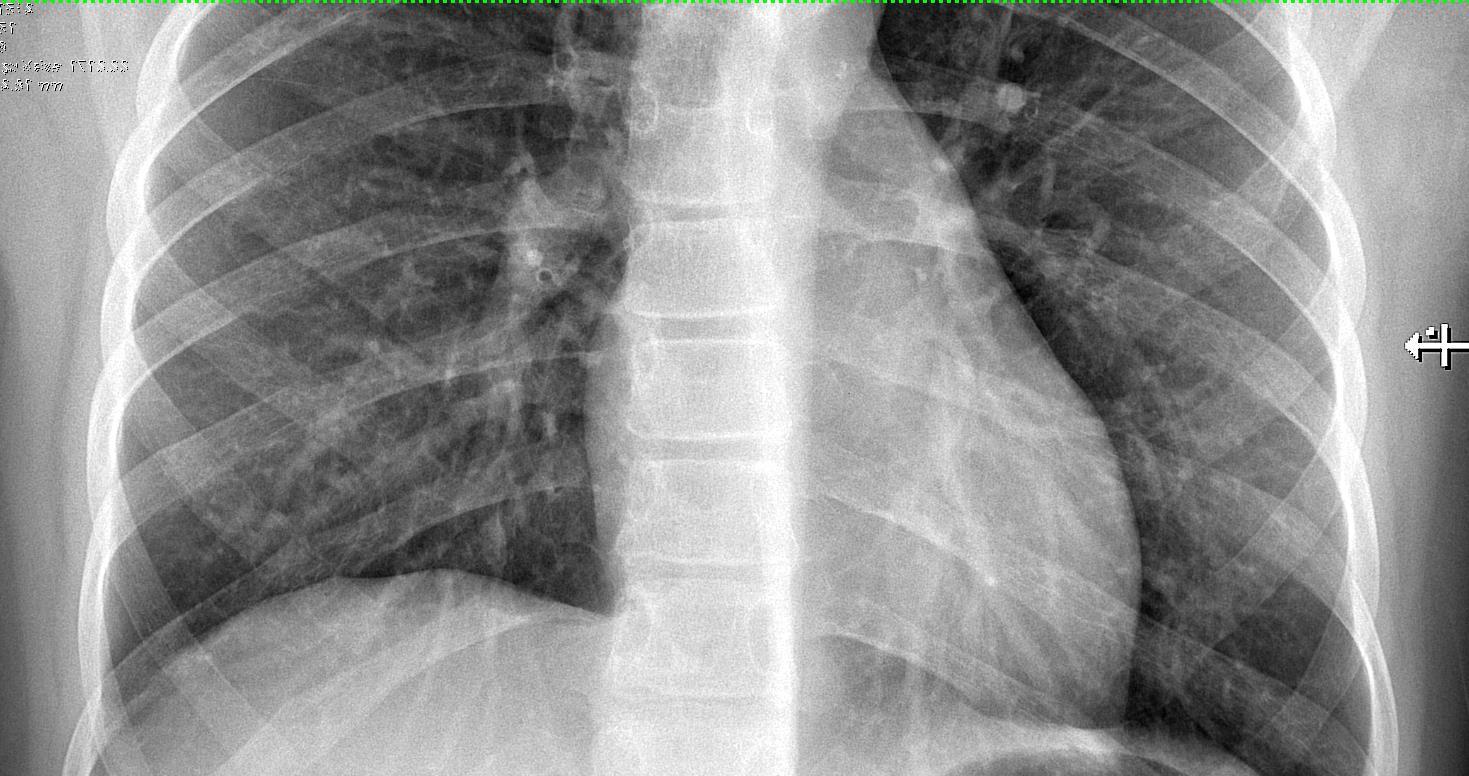

Lung Disorders CXR

COVID 19

• Patchy bilateral GGO, Consolidations or both

• Peripheral and lower lung zone predominance

CT

• Bilateral & multifocal GGO, +/Consolidations or both

• Halo sign

• Peripheral and subpleural

• Bronchovascular thickening

Helpful Imaging Features

• Halo sign (Early)